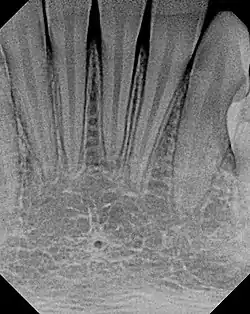

The small lingual foramen (black "hole" in lower portion of picture) as seen on a periapical radiograph of the anterior mandible.

The lingual foramen is a small midline opening on the posterior aspect of the symphysis of the mandible, just above the mental spine. The lingual foramen gives passage to a single small artery formed by the union of two branches of the sublingual arteries (each sublingual artery contributing a single branch).[1]